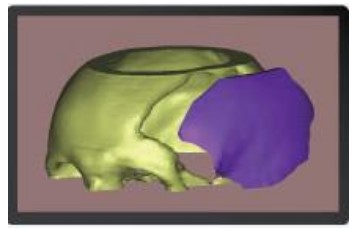

Captura y Modelado 3D

La reconstrucción anatómica se realiza a partir de imágenes obtenidas mediante técnicas de diagnóstico como Tomografía Axial Computada (TAC) o Resonancia Magnética (MRI). Estas imágenes son procesadas con software especializado para modelar en tres dimensiones cualquier región anatómica, incluso con patologías complejas.

Inclusión de Implantes

En el modelado digital 3D se pueden incluir implantes ortopédicos como placas, tornillos, mallas, prótesis y otros dispositivos, diseñados en tamaño real y en relación directa con la anatomía del paciente. Esto permite simular distintos escenarios quirúrgicos antes de la cirugía.

Prototipo Plástico

A partir del modelado 3D digital se obtiene un prototipo plástico impreso en 3D, que respeta fielmente las medidas anatómicas reales. Esto permite al cirujano comprender de forma precisa la patología a tratar y planificar la intervención con mayor seguridad.